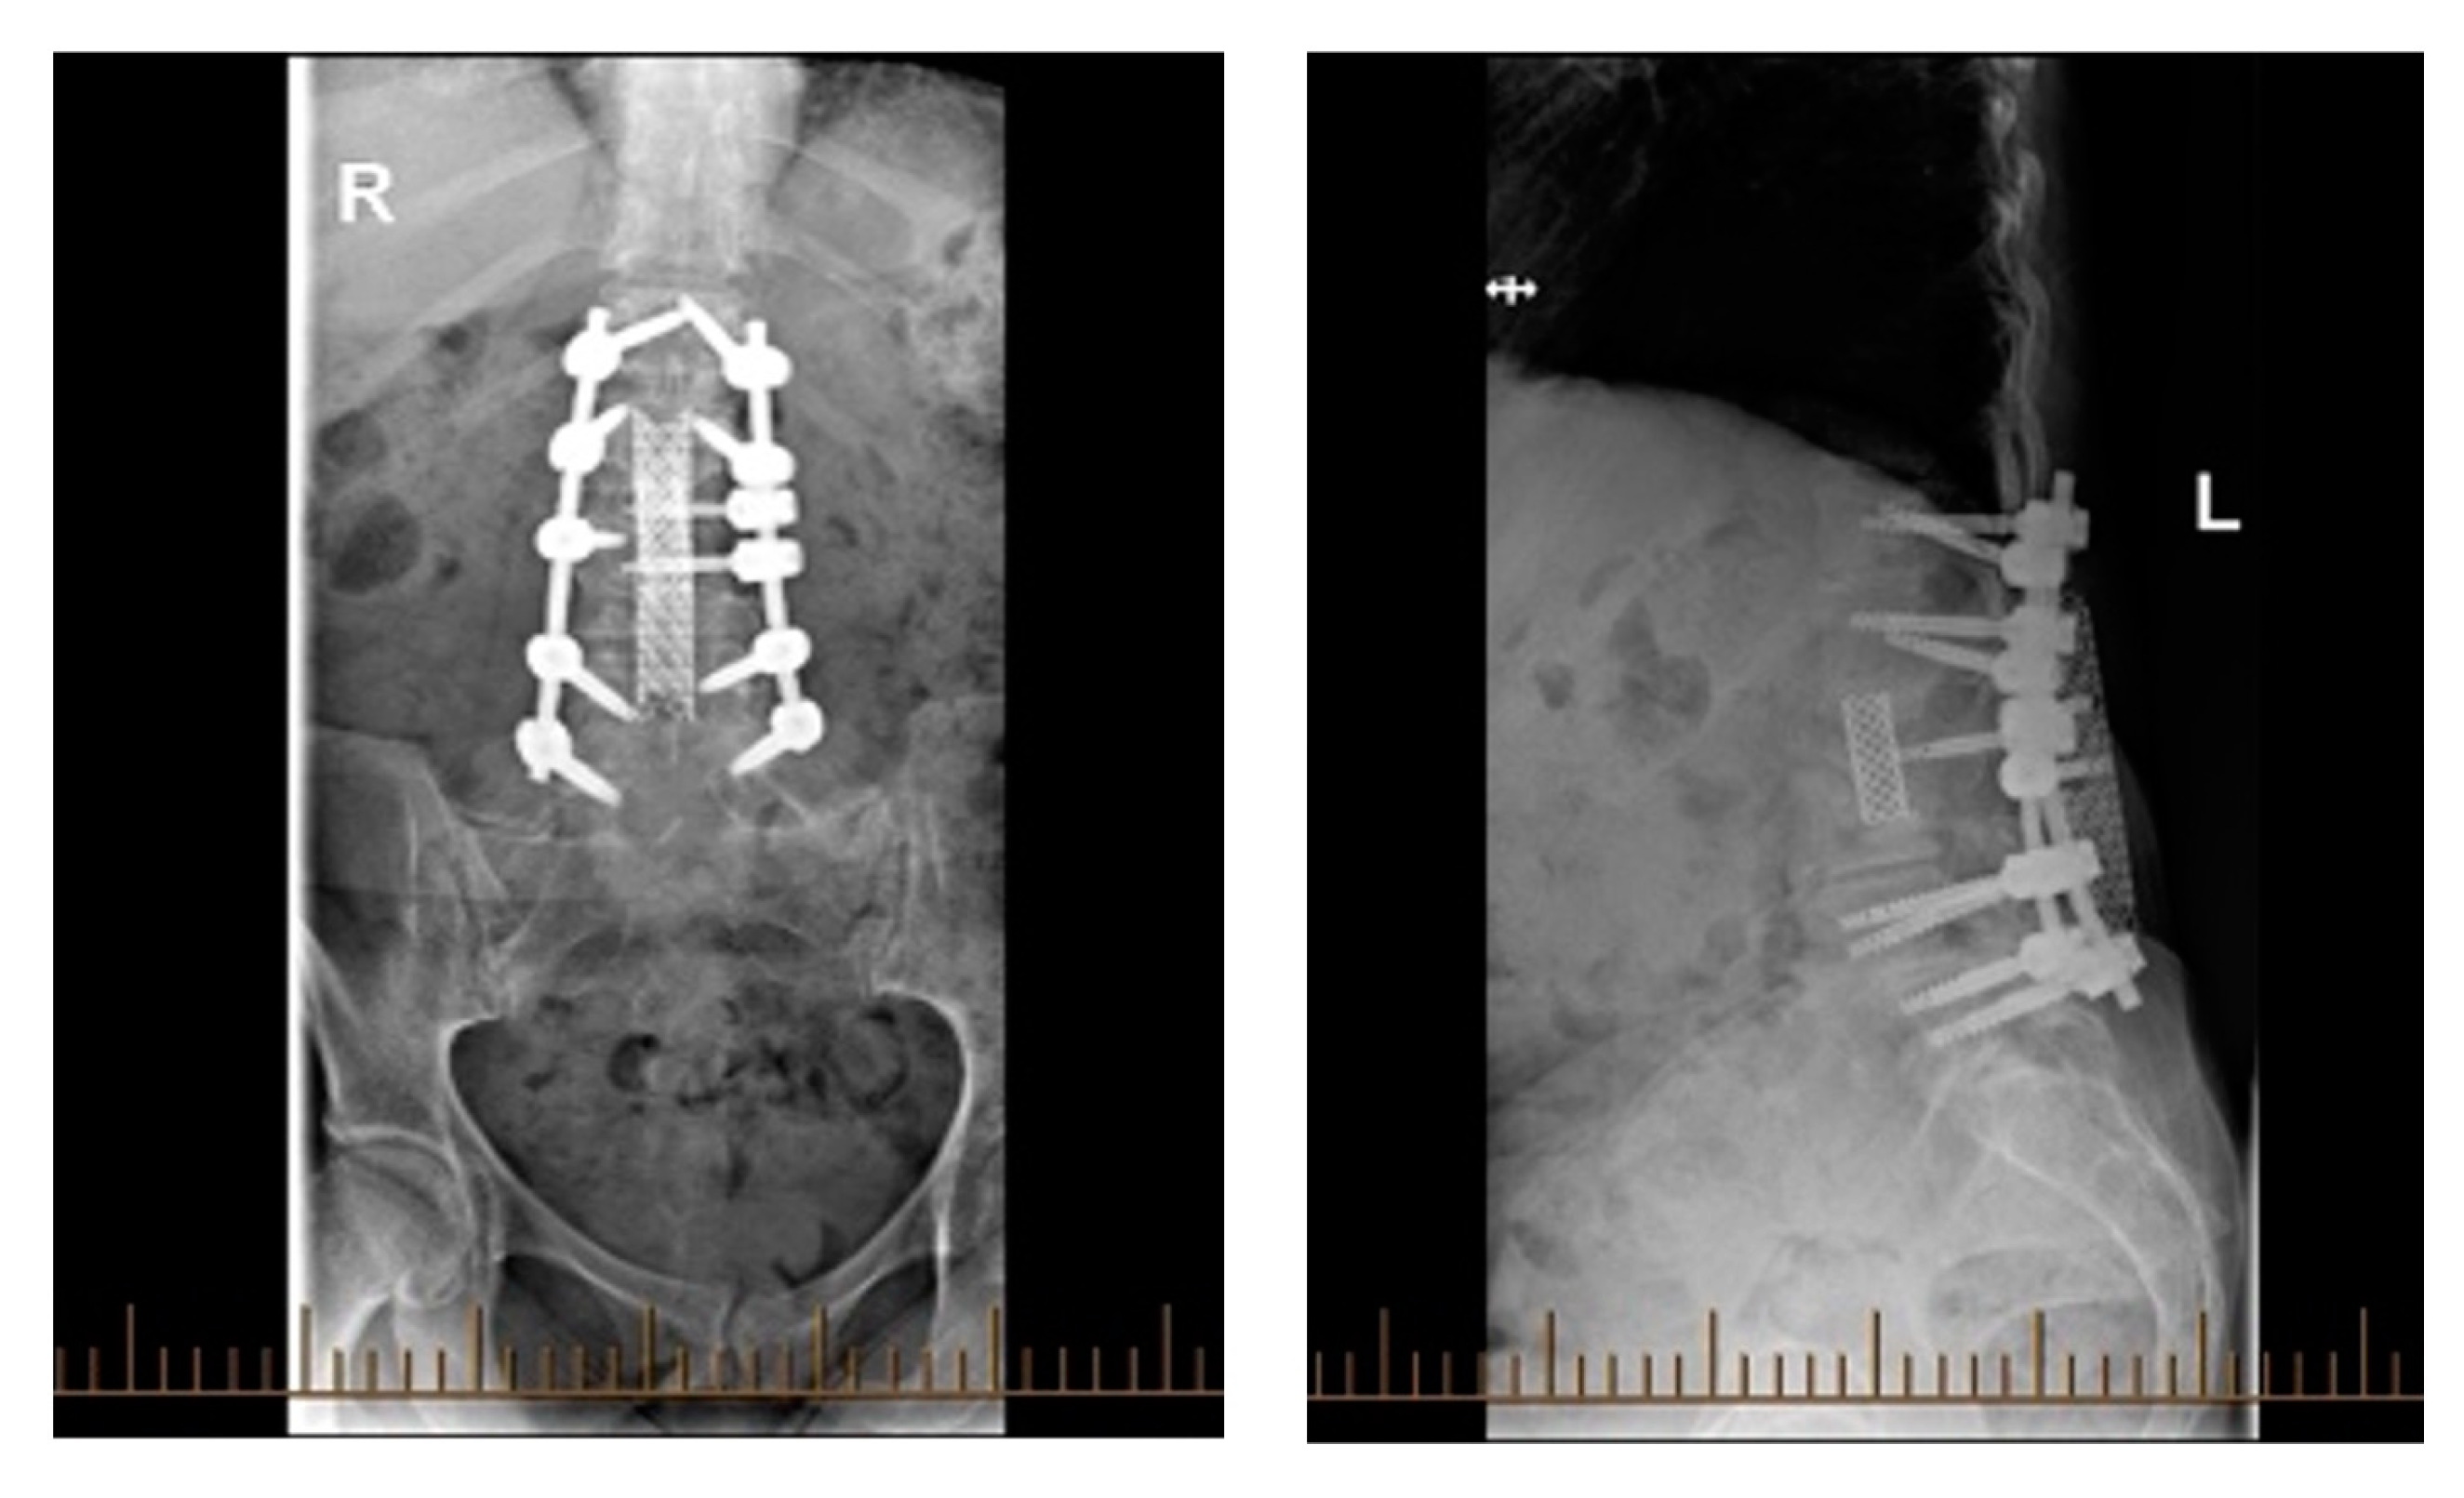

3.2.3. Treatment

3.2.4. Outcomes